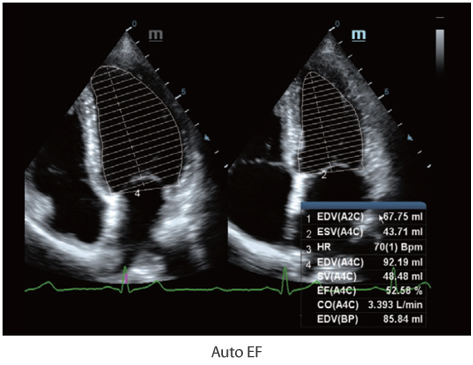

X-Insight es la soluci├│n intuitiva para una mejor visualizaci├│n.

La nueva soluci├│n de Mindray es una excelente transformaci├│n desde la continua comprensi├│n de las necesidades cl├Łnicas del usuario, combinada con la evoluci├│n de la tecnolog├Ła de los ultrasonidos m├Īs puntera. Repleto de vitalidad, con el ├║nico objetivo de visualizar el futuro y evitar los l├Łmites, el ec├│grafo DC-60Exp con X-Insight est├Ī constantemente mejorando con una escalabilidad aumentada. Como un socio personal, el equipo de ultrasonidos DC-60 Exp con X-Insight se centra en lo que verdaderamente importa, ayudando al usuario a administrar su pr├Īctica cl├Łnica con facilidad y seguridad.

Bas├Īndose en una profunda comprensi├│n de las necesidades del usuario, el sistema de ultrasonidos DC-60 Exp con X-Insight est├Ī dise?ado para ofrecer una alta eficiencia con im├Īgenes de precisi├│n, la cual se ve potenciada por una claridad inmediata, una inteligencia excepcional y benefici├Īndose de una c├│moda experiencia.